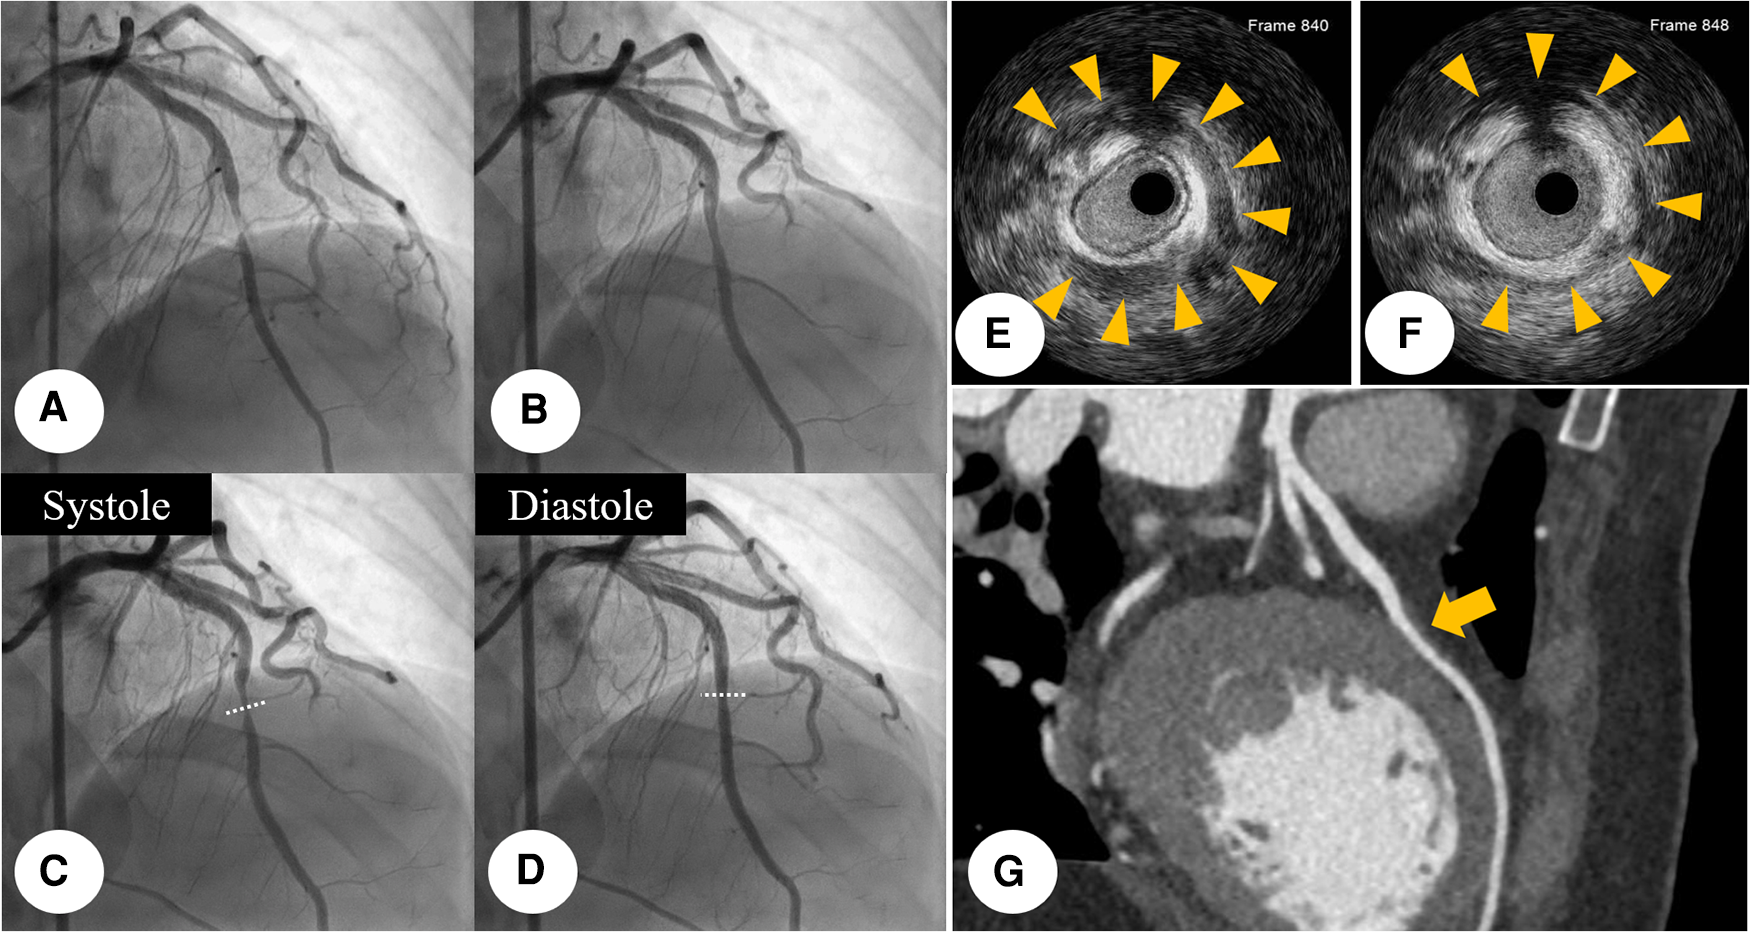

Initial CAG was performed via the right femoral artery at the catheterization laboratory. It revealed near-total occlusion at the middle portion of left anterior descending coronary artery (LAD) with reduced antegrade coronary flow (Figure 2A). After intracoronary nitroglycerin (I-NTG) administration, however, this stenosis was dramatically relieved (Figure 2B), but there was found systolic compression at the same site, suggestive of MB (Figures 2C,D, Supplementary Video S1). In quantitative coronary analysis, the systolic diameter was 0.84 mm and the diastolic diameter was 1.17 mm, which meant that the diameter change from diastole to systole was about 28.2% (Supplementary Figure S2). For the further evaluation, intravascular ultrasound (IVUS) study was examined with a guidance system (Eagle Eye® Platinum RX Digital IVUS Catheter, Volcano Corporation, Rancho Cordova, CA, USA). In IVUS, eccentric compression was seen in the MB segment with a half-moon-like echo-lucent space between the MB segment and epicardial tissue (Figures 2E,F, Supplementary Video S2). There was no definite evidence of atherosclerotic plaque formation within the MB segment. The cross-sectional area at this segment was 4.99 mm2 during the diastole, and 3.42 mm2 during the systole (Supplementary Figure S3). In multiple-slice coronary computed tomography angiography (CCTA), there was seen a coronary segment surrounded by myocardium at the middle portion of LAD (Figure 2G). We concluded that the final diagnosis of this patient was MI with non-obstructive coronary arteries (MINOCA). The patient was transferred to the intensive care unit for the hemodynamic monitoring.

Figure 2

Initial CAG finding: initial CAG demonstrated near-total occlusion (yellowish arrow) at the middle portion of LAD with reduced antegrade coronary flow. (A) This stenosis was dramatically relieved (yellowish arrow), after I-NTG administration (B) After I-NTG administration, systolic compression was seen at the middle portion of LAD, which means MB. (C,D) IVUS was further examined with a guidance system (Eagle Eye® Platinum RX Digital IVUS Catheter, Volcano Corporation, Rancho Cordova, CA, USA), demonstrating eccentric compression with a half-moon-like echo-lucent space between the MB segment and epicardial tissue. (E,F) Multiple-slice CCTA imaging showed a bridged coronary segment surrounded by myocardium at the middle portion of LAD (yellowish arrow). (G) CAG, coronary angiogram; CCTA, coronary computed tomography angiography; I-NTG, intracoronary nitroglycerin; LAD, left anterior descending coronary artery; MB, myocardial bridge.